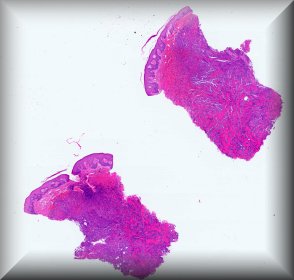

Varón de 77 años con hiperplasia benigna prostática y lesión testicular, detectada durante la exploración prostática. En ecografía, nódulo de 27mm multiloculada, en testículo/epidídmio dcho.